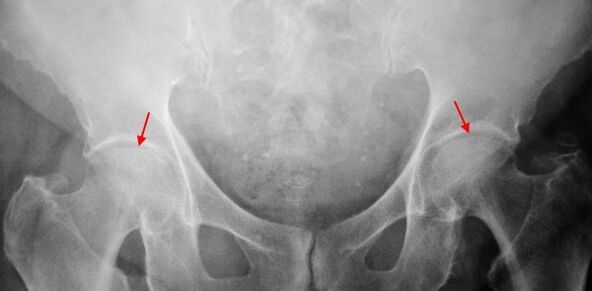

Esimese astme koksartroosi all kannatava patsiendi x -ray korral määratakse kerged muutused: liigese lõhe mõõdukas ebaühtlane kitsenemine, samuti luude kasv atsetabulumi välise või sisemise serva ümber, kui reieluu pea ja kaela muutusi puuduvad.

Teise astme koksartroosi x -ray -piltide korral määratakse liigeselõhe oluline ebaühtlane kitsenemine (rohkem kui poole normaalsest kõrgusest). Reieluupea on mõnevõrra nihutatud ülespoole, deformeerunud ja suureneb ning selle kontuurid muutuvad ebaühtlaseks. Luude kasvu selle koksartroosi astmega ei ilmu mitte ainult sisemisel, vaid ka atsetabulumi välimisel servas ja lähevad kõhrest väljapoole.

Kolmanda astme koksartroosi radiograafidel tuvastatakse liigese lõhe järsk kitsenemine, reie pea hääldatud laienemine ja mitu luude kasvu.

Koksartroosi diagnoosimine põhineb kliinilistel märkidel ja täiendavate uuringute andmetel, mille peamine on radiograafia. Paljudel juhtudel võimaldavad X -Rays kindlaks teha mitte ainult koksartroosi aste, vaid ka selle esinemise põhjus. Näiteks kaeladiafüüsi nurga suurenemine, atsetabulumi stseenid ja lamenemine näitavad düsplaasiat ning reieluu proksimaalse osa kuju muutused on näidatud, et koksartroos on Pertesi tõve või noorusliku epifüsiolüüsi tagajärg. Koksartroosiga patsientide radiograafidel võib tuvastada ka muutusi, mis näitavad vigastusi.